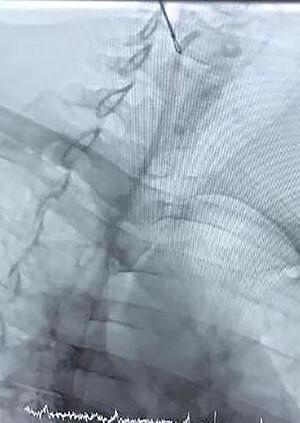

完全植入式化疗端口导管:文献综述及4例报告

Totally implantable catheters tend to be the most popular choice because once installed they allow permanent access to a deep vein, which is gained by puncturing the port rather than a vein. In this article, we explain four cases of chemotherapy port complications: superior vena cava (SVC) syndrome in a metastatic colorectal cancer patient who presented with bilateral mastitis, snare technique for removal of migrated catheter line, carotid artery placement of a port in a 5-year-old child that was referred to our hospital from a pediatric center and adhesive port tip in the heart that finally we left the port . In SVC syndrome, treatment should be guided by the severity of symptoms, etiology of the obstruction, prognosis of the patient and treatment goals. We propose timely removal of port-a-cath following completion of intended chemotherapeutic regimen.

完全植入式导管往往是最受欢迎的选择,因为一旦安装好,它们就能提供对深静脉的永久通路,这种通路是通过穿刺端口而非静脉获得的。在本文中,我们阐述了4例化疗端口并发症:1例转移性结直肠癌患者出现双侧乳腺炎合并上腔静脉(SVC)综合征;1例采用圈套技术取出移位的导管;1例5岁儿童从儿科中心转诊至我院,其端口植入到了颈动脉;还有1例心脏内端口尖端粘连,最终我们保留了该端口。对于SVC综合征,治疗应根据症状严重程度、梗阻病因、患者预后及治疗目标来指导。我们建议在完成预定化疗方案后及时取出植入式静脉输液港。